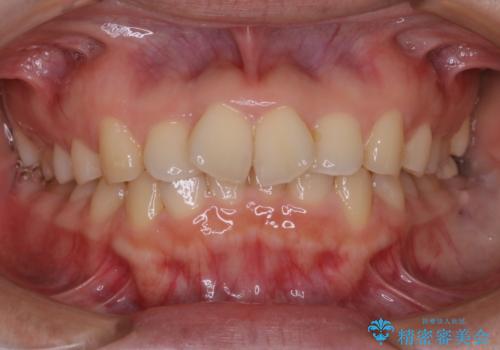

前歯が内側に入っている:インビザライン治療

- 上の前歯は内側に入っていることが気になりご相談にいらした方です。インビザラインにて治療を行いました。

1週間でのマウスピース交換を指示していましたが、20時間以上使えない時があると不安との事で、2週間ごとの交換にしていました(実際はほとんど20時間以上使用できていたようです)。治療終了まで時間はかかりましたが、最終的に綺麗に並べることができ、大変喜んでいただけました。